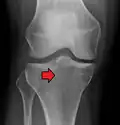

Subtle tibial plateau fracture on an AP X ray of the knee -

In all injuries to the tibial plateau radiographs (commonly called x-rays) are imperative. Computed tomography scans are not always necessary but are sometimes critical for evaluating degree of fracture and determining a treatment plan that would not be possible with plain radiographs.[10] Magnetic Resonance images are the diagnostic modality of choice when meniscal, ligamentous and soft tissue injuries are suspected.[11][12] CT angiography should be considered if there is alteration of the distal pulses or concern about arterial injury.